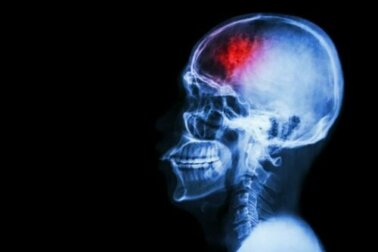

Ein Schlaganfall tritt auf, wenn die Blutversorgung in einem Bereich des Gehirns stark behindert oder vollkommen unterbrochen ist. Infolgedessen kann es zu Schädigungen oder gar dem Absterben von Neuronen kommen. Um dies zu verhindern, wollen wir dir heute verschiedene Maßnahmen vorstellen, die du zur Vorbeugung von Schlaganfällen ergreifen kannst.

Ein Schlaganfall ist eine zerebrovaskuläre Erkrankung, die die Blutgefäße betrifft, welche das Gehirn mit Blut versorgen. Ein Schlaganfall tritt auf, wenn ein Blutgefäß reißt oder durch ein Gerinnsel oder ein anderes Partikel blockiert wird.

Wie ein Artikel im MSD Manual erklärt, wird ein Teil des Gehirns durch diese Ruptur oder Blockade nicht mehr mit der erforderlichen Menge an Blut, Sauerstoff und Glukose versorgt. Infolgedessen wird die Sauerstoffversorgung der Nervenzellen im betroffenen Hirnareal unterbrochen. Sie können nicht mehr funktionieren und sterben innerhalb weniger Minuten ab.